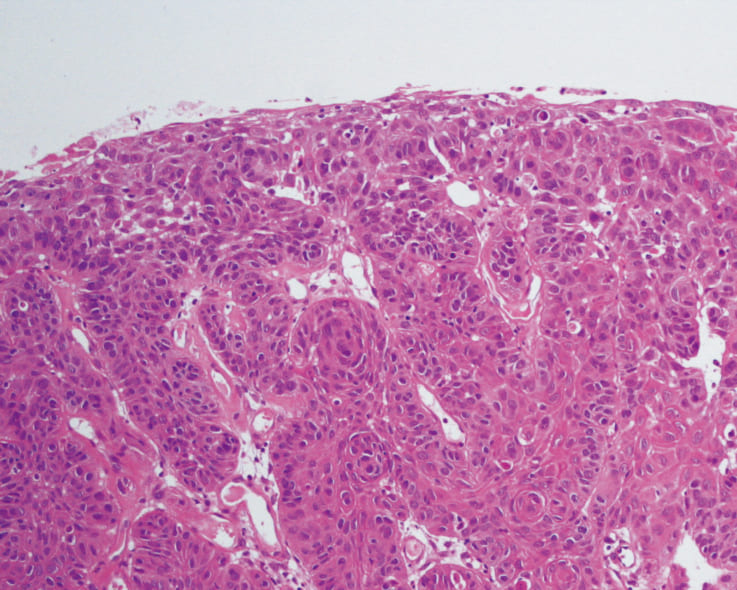

pathology

The patient visited a local hospital complaining hoarseness and was then referred to us. A reddish tumor mass was recognized in the left vocal cord and the white light close-focus view identified abnormal vascular proliferation. Weaving and dilatation of abnormal vascular proliferation were more clearly visualized in NBI observation, thereby leading to a diagnosis of a malignant tumor. The lesion was treated with laser depolarization and pathologically diagnosed as a moderately-differentiated squamous cell carcinoma.